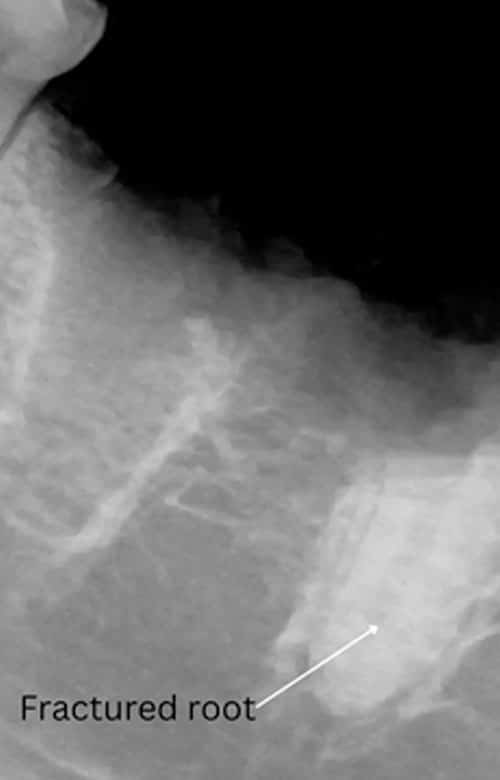

Digital dental X-rays are also crucial after tooth extractions. Although our experienced doctor performs extractions with great care, X-rays allow us to confirm that no root fragments remain and that the extraction site is complete. Without X-rays, it would be impossible to verify the full removal of a tooth.